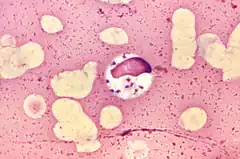

Leishmania est un genre de Protozoaire proche des trypanosomes. C'est un parasite des mammifères transmis par la piqure de phlébotomes et responsable d'une maladie, la leishmaniose. Il existe plus de 20 espèces de Leishmania.

Leishmania cells have two morphological forms: promastigote (with an anterior flagellum) in the insect host, and amastigote (without flagella) in the vertebrate host. Infections are regarded as cutaneous, mucocutaneous, or visceral: